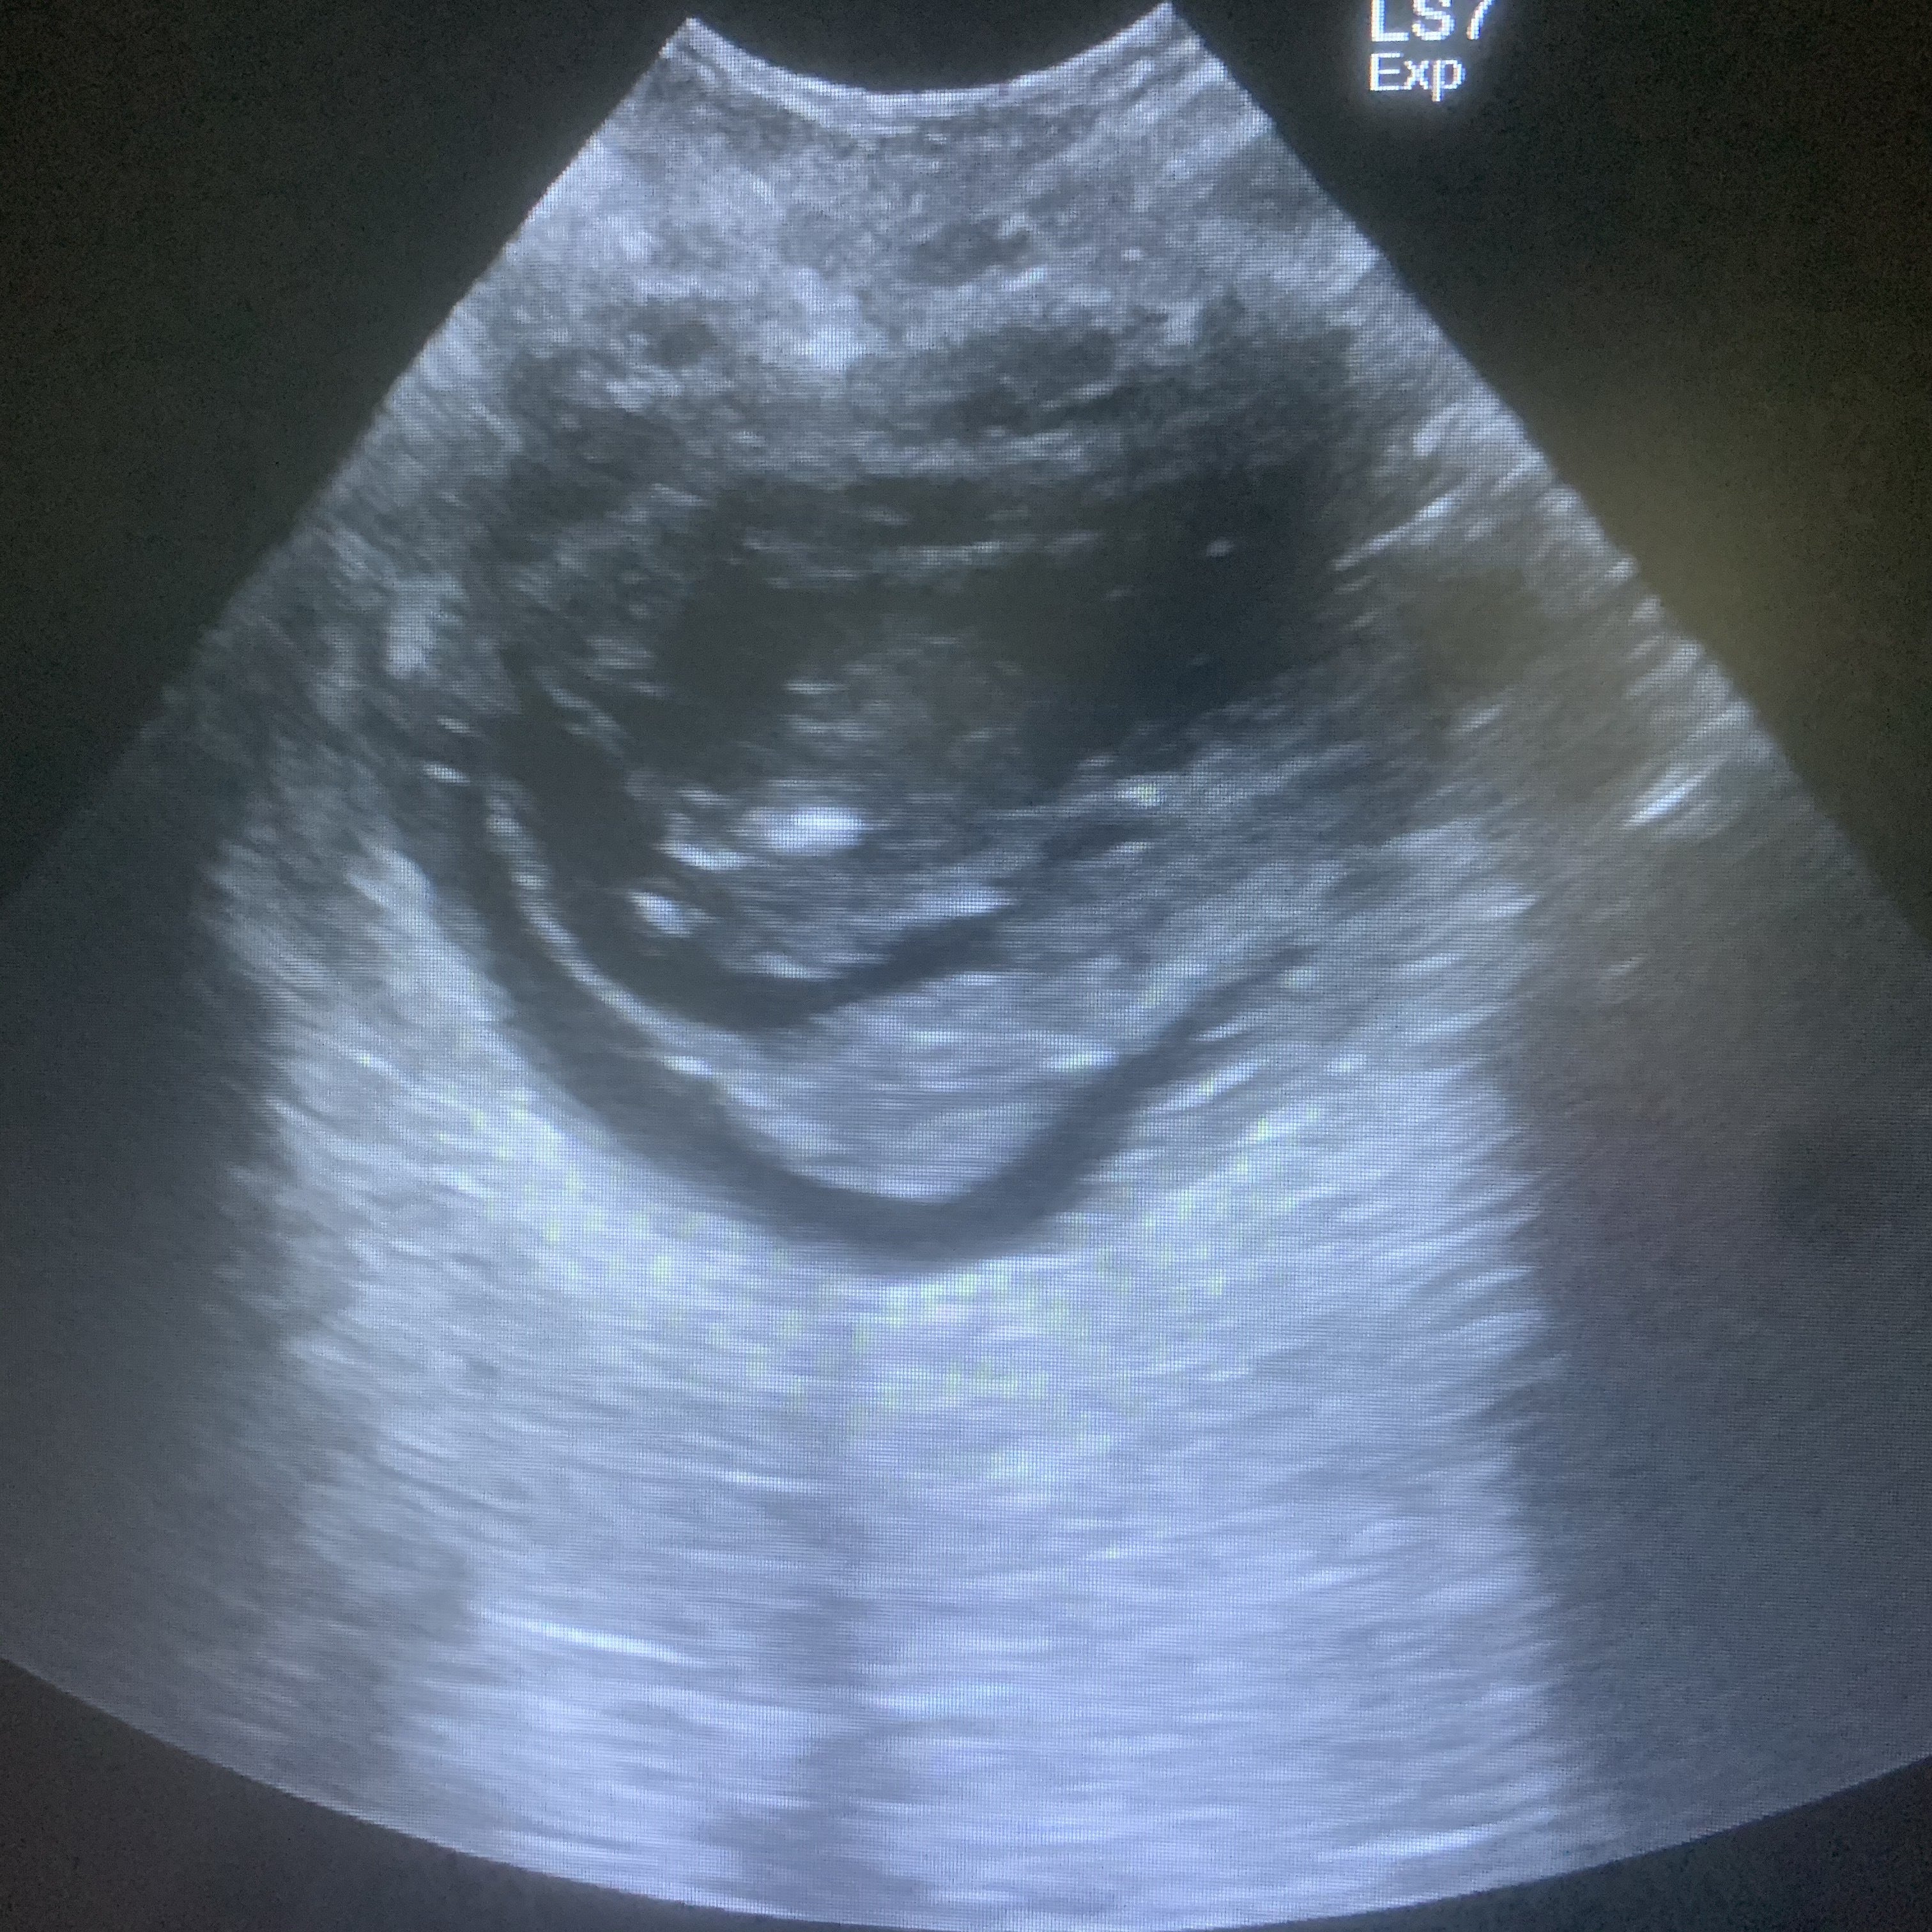

エコーで確認したら膀胱にうっすら何かが。

エコーで見たら結石が尿道で詰まっている。

素人のわたしでもわかる程はっきり写っていた。

絵の下の数字が抜いた量。合計200ml。

昨日エコーで見たときより更に石が増えて

尿道に行列を作っている。(絵を参照)

8日に見たエコーのぼんやりした影は

出来たばっかりの結晶で、

それがいきむことで崩れて

一気に尿道に詰まったのだろうと。

エコーを毎日して状況を確認しているそう。

写真をたくさん見せてもらったうちの1枚。

少しずつ尿が黄色くなってきていると。

膀胱の腫れはあり。

粘膜が引いてきているので改善はしている。

エコー検査で膀胱内に影が確認されました。

5月27日に摘出した壊死した組織が再び

蓄積している疑いがあるそうです。